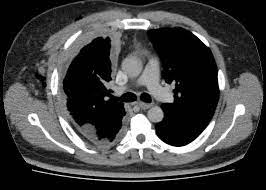

Tasas de procedimientos posteriores y complicaciones asociadas con el rastreo de cáncer de pulmón en la práctica clínica

En la práctica habitual, las tasas de procedimientos posteriores y de complicaciones del rastreo del cáncer de pulmón con tomografía computada son sustancialmente más altas que las observadas en el ensayo clínico NLST. Es probable que sea necesario evaluar y mejorar la gestión del diagnóstico para garantizar que los beneficios de las pruebas de detección superen los posibles daños. Annals of Internal Medicine, 2 de enero de 2024.